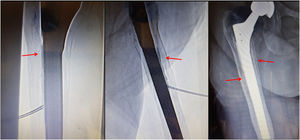

Percutaneous cementationPatients who are candidates for FMP must have undergone a conventional radiology examination and a computed tomography (CT) scan to determine the ‘target’ area to be filled with cement at the level of the femoral stem (metaphyseal-diaphyseal or diaphyseal area) where we detect a greater degree of osteolysis. It is not necessary to administer heparin; on the contrary, the administration of anticoagulants should be stopped 24–72 h beforehand (depending on whether it is heparin or aspirin which requires a withdrawal time of 24 h, or acenocoumarol, dabigatran, warfarin which need longer periods). Allergies to contrast, tantalum, antibiotics or cement should also be ruled out. It is advisable to administer a prophylactic intravenous cephalosporin (ceftazidime 1 g) within 30 min. prior to the procedure. The technique is performed under general anaesthetic or nerve block, in strict sterile conditions in a vascular operating room, CT room or in the operating theatre with fluoroscopic monitoring of both the needle placement and cement distribution. The preferred access point for the intervention is lateral or anterolateral through the vastus lateralis muscle (at roughly 2 and 3 o'clock for a left hip), to avoid both the rectus femoris tendon (at 12 o'clock for a left hip) and the neurovascular pathway (posteromedial). Ultrasound-guided local anaesthesia (Bupivacaine) is administered by percutaneous puncture using a 22G needle measuring 9 or 15 cm in length, depending on the patient's phenotype. The needle is inserted until it reaches the femoral diaphyseal cortex adjacent to the ‘target’ area. Through the same percutaneous access, a vertebroplasty (VP) needle is introduced into the described area, perforating the femoral cortex until it makes contact with the prosthetic stem or the cement mantle in the case of a cemented prosthesis (Fig. 1). At this time it is advisable to perform a fine needle aspiration (FNA) puncture using the VP cannula so that periprosthetic samples can be sent for microbiological cultures (in aerobic + anaerobic + sterile S16 bottles) and cytology smears (if sufficient material is available) to obtain additional information on previously undetected infection or other complications such as granulomatous disease (particle disease) or an adverse reaction to metals. There is then the option of using ionic radiopaque contrast to check that the needle tip is positioned at the chosen ‘target’ area. Fluoroscopy with 2D rotation or CT scanning can ensure highly accurate positioning. The next step is to inject sterile poly(methyl methacrylate) (PMMA) cement through the VP cannula. The cement has a shorter solidification time here than in VP, as a more fluid distribution is sought in the stem area, and it is mixed with gentamicin (to reduce the risk of infection). In our case we did not inject fibrinolytic enzymes. Instead, the formation of the cement around the stem was monitored by imaging. The metaphyseal-diaphyseal femoral area is the primary focus for cementation as it provides the greatest stability. This is followed by the diaphyseal area (Fig. 2). No cement must reach the level of the prosthesis joint (this could lead to limited mobility or affect the friction torque), or any previous femoral bone defects (previous implant sites). Once the periprosthetic area is sufficiently filled (assessed by imaging; Fig. 3), the PMMA injection is stopped and the VP needle is carefully removed, blocking the PMMA residue with the mandrel to prevent it from migrating along the needle path to the soft tissues. In this final phase, sedation is discontinued if it is deemed no longer necessary for the patient. There is also the option of using a CT scan to monitor periprosthetic filling with cement and rule out local leakage. Pulmonary embolisms are a well-known complication of VP, but have not been reported for FMP. This is probably because femoral target areas are not as vascularised as vertebral bodies.

Femoroplasty technique. Sedation and local anaesthesia. Needles (10–13 G) guided by CT or fluoroscopy. Strict asepsis. Sometimes a hammer or drill is necessary to perforate the cortex, if it is not possible to do so by hand. Anterolateral access (to avoid the rectus femoris tendon). After mixing PMMA cement + tantalum (radiopaque) + antibiotic (gentamicin 2 g), there are approximately three minutes before it consolidates. Image-guided monitoring can rule out leakage and proximal progression.

Femoroplasty technique. Image-guided monitoring. Patient aged 81 years. The fluoroscopic image shows that the vertebroplasty needle is located in the prosthetic stem area, with the bevel facing the area of interest. Different projections confirm the linear progression of the cement in the stem area during the cement injection (arrows).